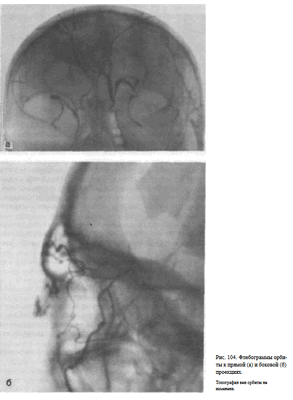

УКЛАДКИ ФЛЕБОГРАФИЯ ОРБИТЫ

Назначение исследования — определение объемного процесса в полости глазницы на основании изменения топографии венозной сети, главным образом верхней глазничной вены.

Методика исследования. Под местной анестезией производят пункцию лобной или лицевой вены. Через иглу вводят полихлорвиниловый катетер с наружным диаметром 0,8—0,9 мм. Катетер фиксируют. Широкой резиновой лентой сдавливают мягкие ткани лба с целью закрытия просвета лобных вен.

Поперечную вену носа и лицевую вену сдавливают с помощью ватных подушечек. После введения 1—2 мл 0,5 % раствора новокаина максимально быстро—за 1—1,5 с—вливают 3—4 мл 50% раствора гипака и производят серию рентгенограмм в задней обзорной и боковой проекциях. Для этого используют специальный ангиографический комплекс, включающий две рентгеновские трубки и две приставки для быстрой смены кассет. При отсутствии такого комплекса после введения контрастного вещества поочередно выполняют прямой и боковой снимки.

Информативность исследования. Топография верхней глазничной вены постоянна. В норме на флебограмме орбиты в боковой проекции верхняя глазничная вена выявляется под верхней ее стенкой. Она имеет плавные изгибы. Часто видны коллатеральные вены, соединяющие ее с нижней глазничной веной, менее постоянной в своей топографии. На флебограмме

орбиты в прямой задней проекции верхняя глазничная вена отображается в форме ромба (рис. 104, а, 6). Отклонение в пробеге верхней глазничной вены, оттеснение ее, а также обрыв, как правило, связаны с объемным процессом в полости глазницы.